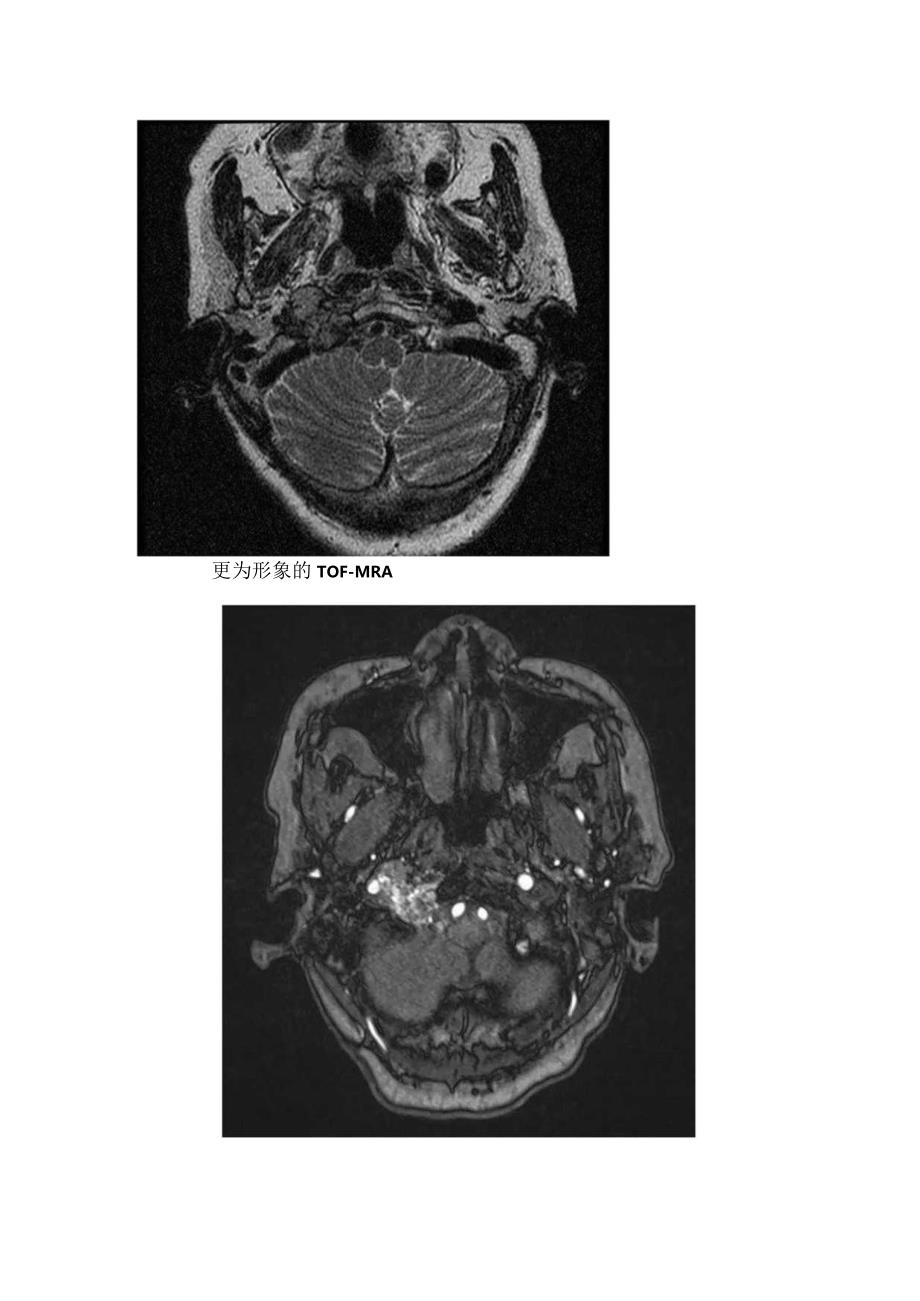

1、胡椒盐征影像表现、临床病理及鉴别诊断胡椒盐征:血管球瘤中有多数迂曲条状及点状血管流空影,MRI增强扫描不强化,肿瘤实质明显强化,称为“椒盐”征。“椒”是低信号血管流空影;“盐”是指高信号的点状出血。横断位所见患者女性,72岁,反复头痛、耳鸣1年余,加重1周。更为形象的TOF-MRAP同一患者CT分析与讨论颈静脉球瘤,起源于颈静脉球壁的化学感受器,属副神经节细胞来源的一类非嗜倍性副神经节瘤(化学感受器瘤),为良性血管性肿瘤,但其生长方式呈恶性。多为无功能性肿瘤,功能性颈静脉球瘤少见。嗜倍性副神经节瘤好发于肾上腺,也叫嗜倍细胞瘤。非嗜倍性副神经节瘤(化学感受器瘤),好发于头颈部,如颈动脉分叉(即颈

2、动脉体瘤)、颈部迷走神经、颈静脉球(即颈静脉球瘤)和中耳鼓室(鼓室球瘤),少数来自鼻咽、喉腔、翼腭窝等。在MRl检查中,颈静脉球瘤除发生部位较特殊外,信号变化,内部血管结构和增强强化形式等有助于该病的诊断。肿瘤实质在T2WI则多数呈明显高信号,TlWI多呈中等或偏低信号,TIWl增强扫描呈明显均匀强化,在多个序列中可见椒盐征,即在肿瘤实质中可见点,条状的无信号流空血管影。肿瘤直径较大时出现此征象的几率高,MRA可发现瘤区有异常血管。在病理组织学上,肿瘤由I型的主细胞和Il型支持细胞构成,主细胞簇由富含大量血管腔的纤维基质分隔,这些血管形成很多毛细血管前动、静脉瘦,这些组织、病理学特点是该类肿瘤MR信号变化及椒盐征的基础。鉴别诊断:1、脑膜瘤:发生颈静脉孔区的脑膜瘤需同颈静脉球瘤鉴别。脑膜瘤多数信号常较均匀,在T2WI上信号多为等或稍高信号,TlWI上多为等或稍低信号,增强扫描常明显均匀强化,有时可见钙化、脑膜尾征等,囊变少见。2、2、IXXl对颅神经起源的肿瘤神经瘤:二者鉴别较困难,较大的神经鞘瘤坏死、囊变常见,而颈静脉球瘤坏死囊变较少,常见椒盐征。